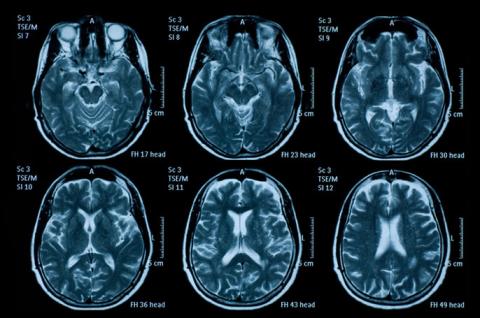

Digital Models of Retinal Vasculature for 3D Printed Phantoms

Digital model available on NIH's 3D Print Exchange site that can be used to fabricate tissue simulating phantoms with biomimetic vascular structures derived from a clinical image

Program Areas:

Medical Imaging and Diagnostics